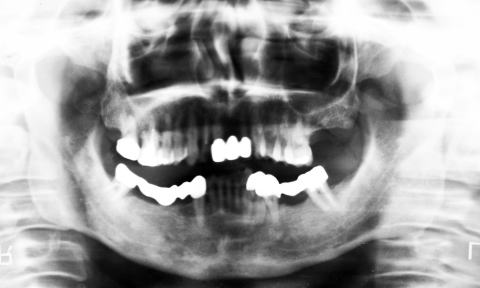

(図1)初診時(1975年10月15日)、38歳。歯肉出血が主訴で紹介された。当時、歯周疾患治治療は一部の臨床家以外はあまり関心が払われていなかった

(図2)初診時(1975年10月15日)、38歳。まず徹底的なPlaque Controlから始めた